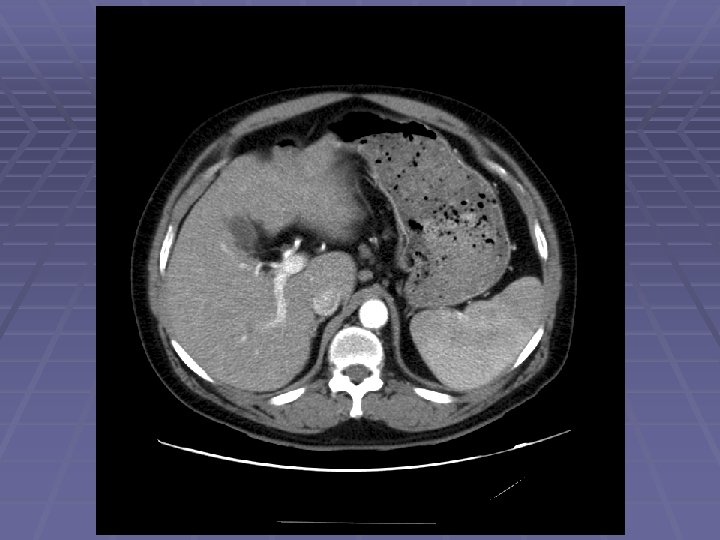

EUS Evaluation of Left Lobe of Liver